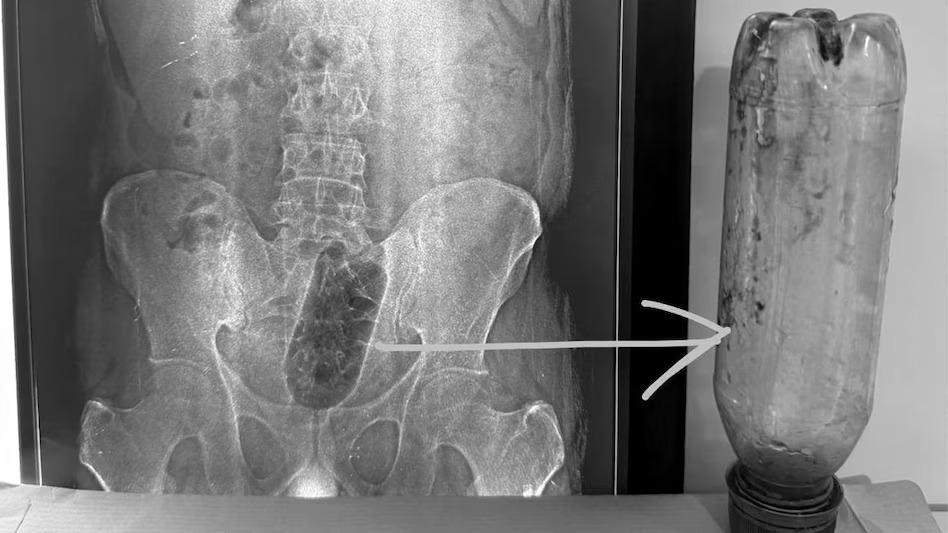

जानकारी के मुताबिक, साकेत कॉलोनी निवासी युवक करीब 36 घंटे तक दर्द सहता रहा. जब तकलीफ ज्यादा बढ़ी तो वह अस्पताल पहुंचा. जांच के दौरान डॉक्टरों ने एक्स-रे कराया, जिसमें साफ हुआ कि उसके मलाशय के भीतर एक लीटर की प्लास्टिक बोतल फंसी हुई है. इसके बाद उसे तुरंत इमरजेंसी में भर्ती कर लिया गया.

अस्पताल के वरिष्ठ सर्जन डॉ. सुनील शर्मा के मुताबिक, मामला बेहद संवेदनशील था, क्योंकि बोतल निकालते समय यह ध्यान रखना जरूरी था कि आंत या मलाशय को गंभीर नुकसान न पहुंचे. डॉक्टरों की टीम ने सावधानी से ऑपरेशन किया और करीब एक घंटे 10 मिनट की मशक्कत के बाद बोतल को बाहर निकाल लिया.